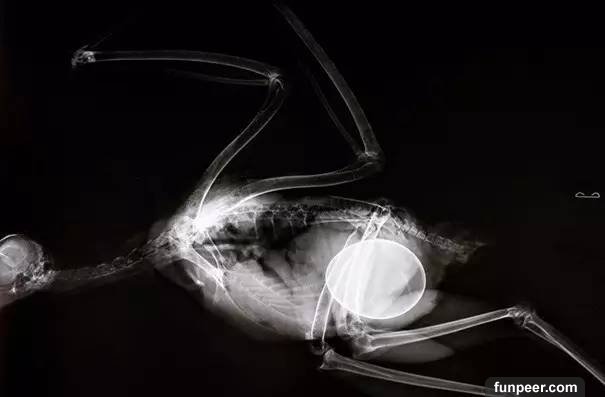

某種蜥蜴,它肚子裡的蛋數量相當多

猴子的懷孕照,僅僅這樣看和人類無異